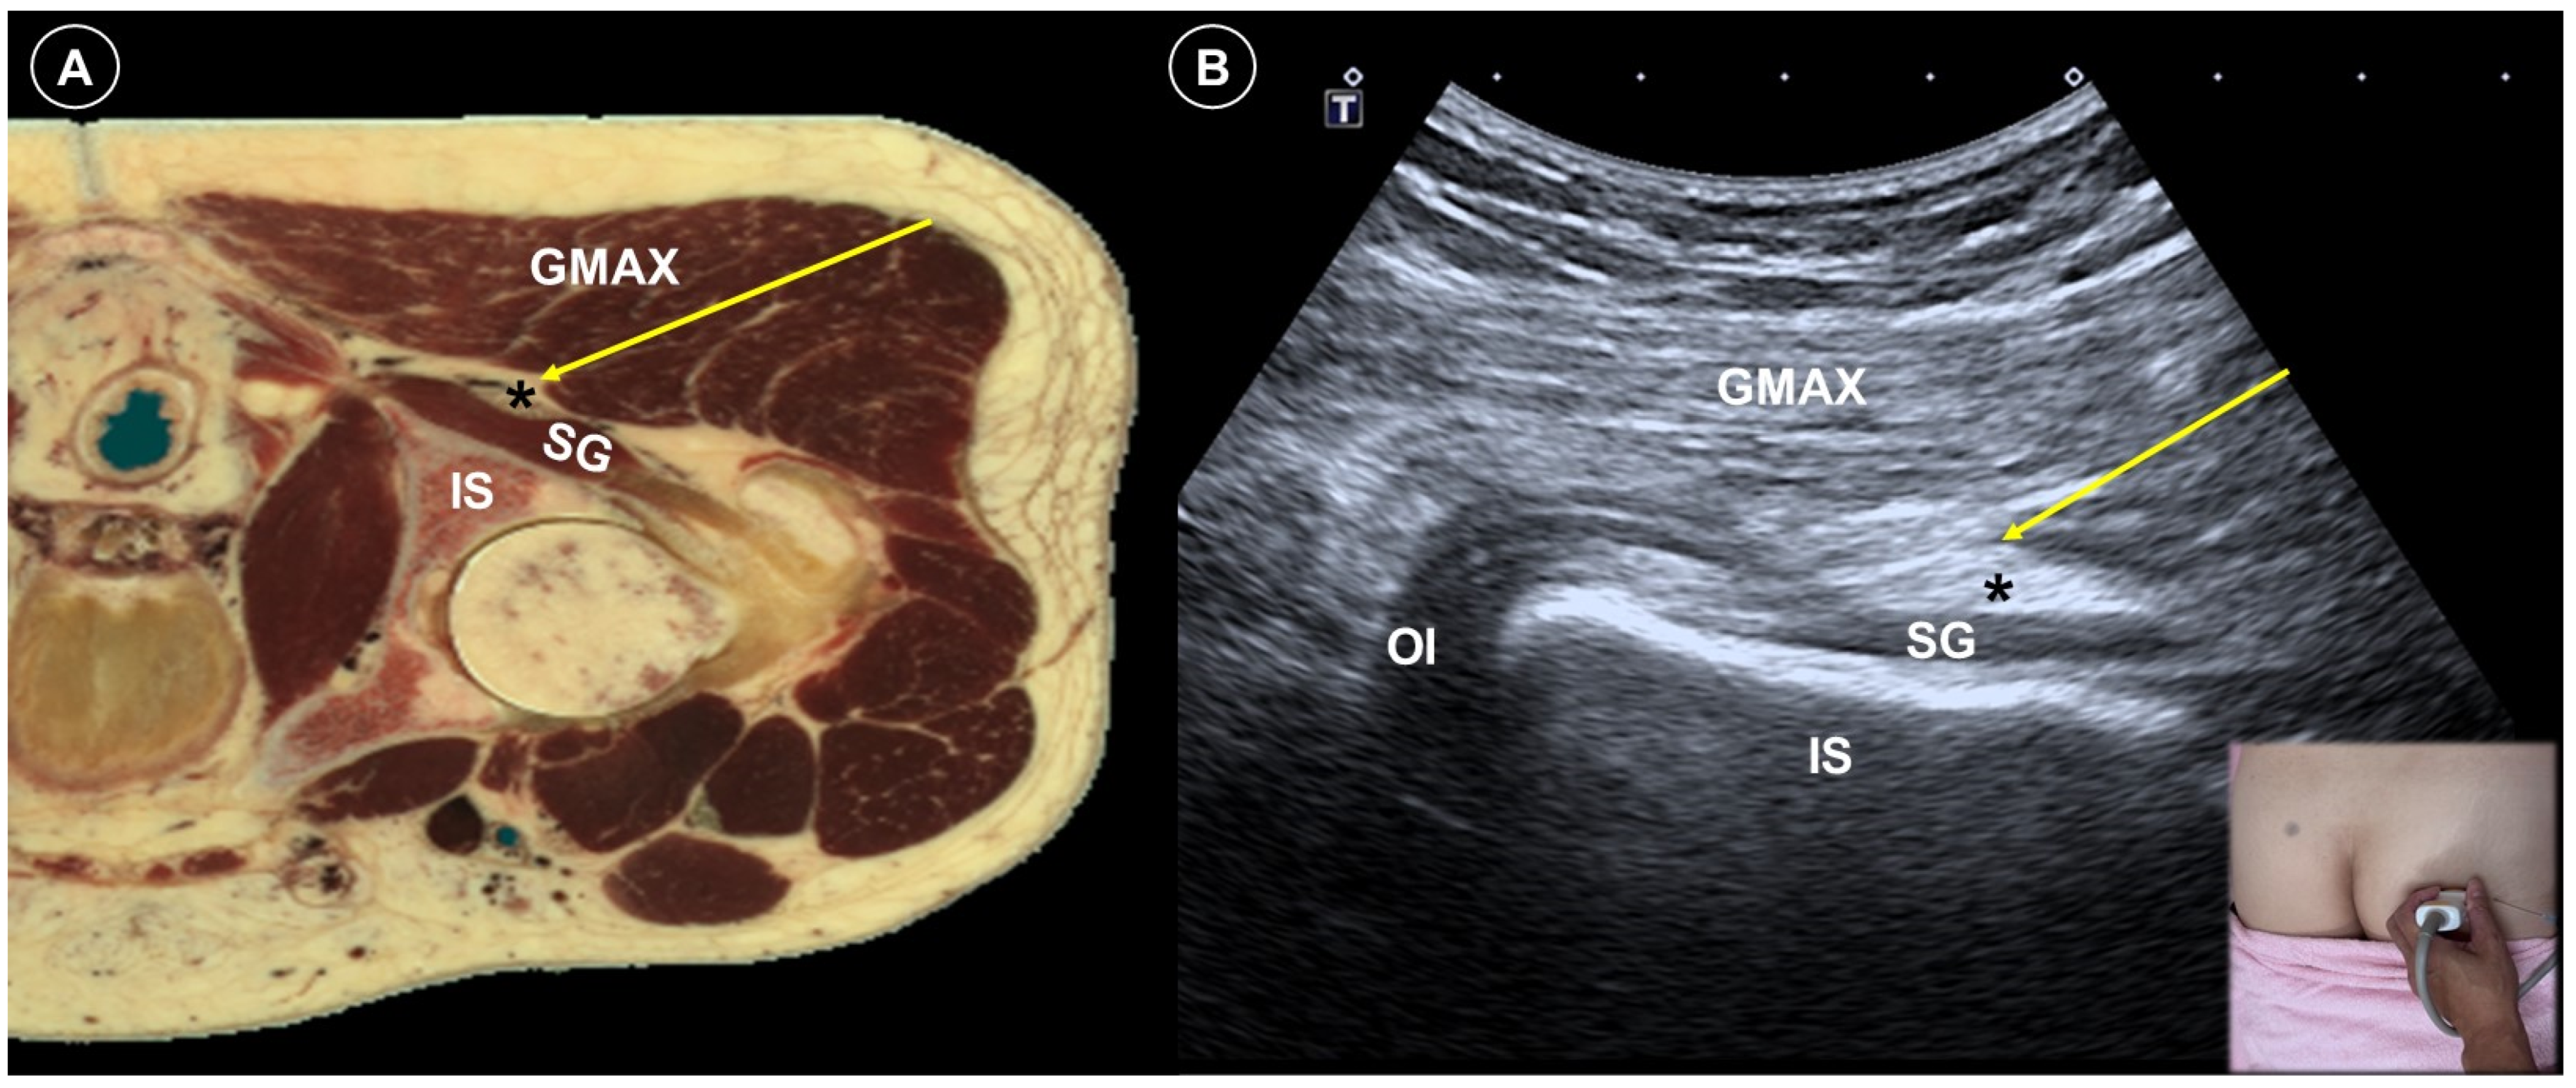

| Post-amputation pain | Stump pain and phantom limb pain | Multifactorial, including neuromas, nerve damage, sensitization |

| Significant pain reduction by PNS (RCT), nerve block/PRF (case study) | Avoid direct injection into the nerve | |